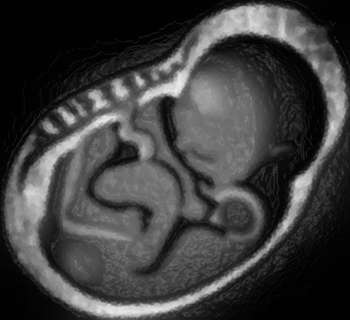

Скандально известный специалист по лечению бесплодия Панайотис Завос (Panayiotis Zavos) вчера выступил с заявлением о том, что он получил путем клонирования 14 человеческих эмбрионов и перенес 11 из них четырем женщинам для вынашивания.

Как рассказал Завос в интервью британской газете The Independent, ни один из переносов не закончился развивающейся беременностью, однако была сделана видеозапись процесса создания клонированных эмбрионов. Автор записи, режиссер-документалист, подтвердил корреспонденту The Independent, что клонирование действительно было проведено, и что клоны были перенесены женщинам для вынашивания.